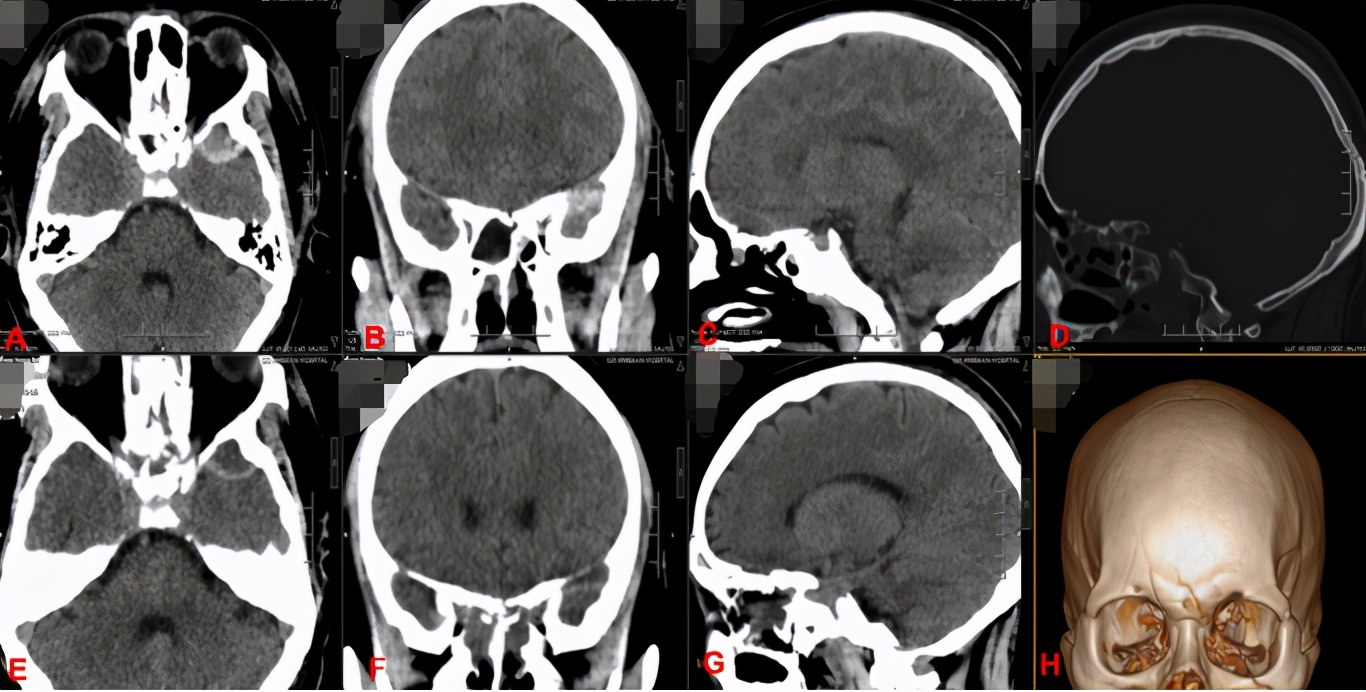

图A、B、C、D、H所示为患者发病后出现颅骨多发骨折,视神经受压。

图E、F、G所示为患者术后改善情况。